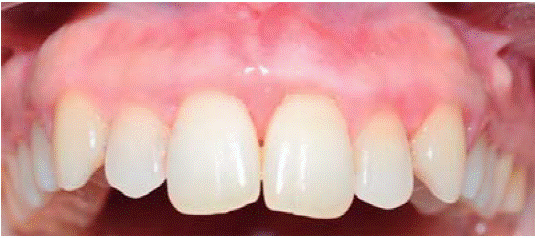

Al examen clínico se observa lesión gingival inflamatoria a nivel de las piezas 1.1 y 2.1, de aproximadamente 9 X 9 mm, cubriendo un tercio de la corona clínica, de consistencia firme, lobulada, textura rugosa, sangrante ante el estímulo y asintomática (Figura 9). A la evaluación periodontal no presentaba bolsas periodontales, sin embargo, se observó presencia de placa, obteniéndose un índice de higiene oral (O'Leary) de 50%.

Al examen radiográfico se observó alteración de la cresta ósea entre las piezas 1.1 y 2.1 (Figura 10).

Diagnóstico presuntivo: granuloma piógeno.

Tratamiento: primera sesión de instrucción de higiene oral seguido de biopsia excisional de lesión y gingivoplastia (Figuras 11 y 12).